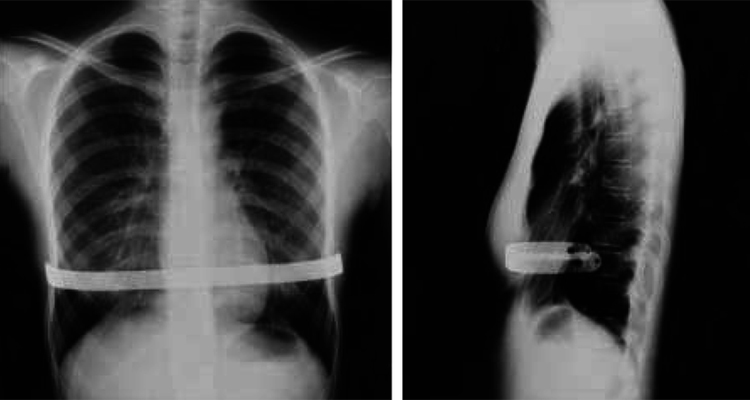

1.4 Chụp X quang sau mổ